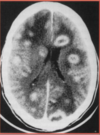

**_NOTE O EDEMA PERI LESIONAL._** **_A HIPOTESE É : NEUROTOXOPLASMOSE._** **_LEMBRAR : SULFADIAZINA + PIRAMI_** **_CLINDA : SE ALÉRGICO._**